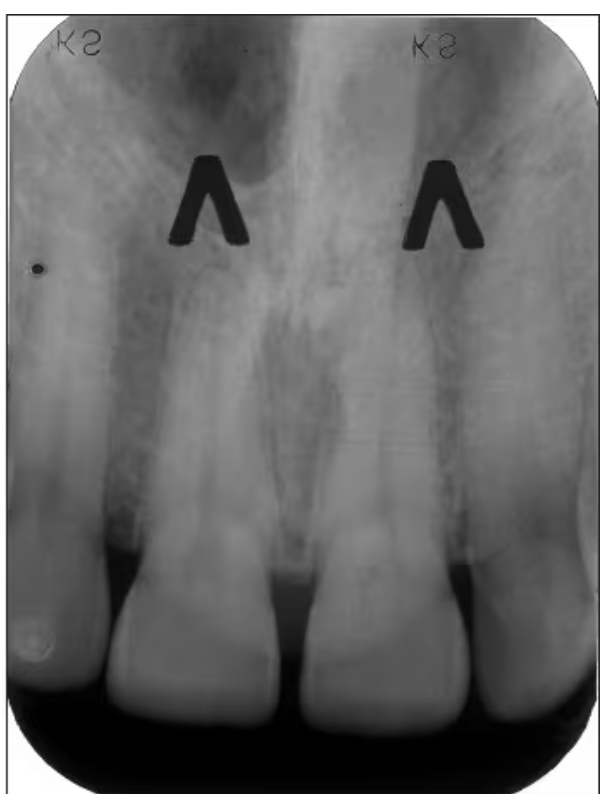

Inverted Y

Depicts where the nasal fossa crosses the maxillary sinus (the boundary between them are shaped like a upside down Y)

Anterior Nasal Spine

Appears “V-shaped” or “triangular point”

Is a bony projection located at the base of the nasal septum in the maxillary midline